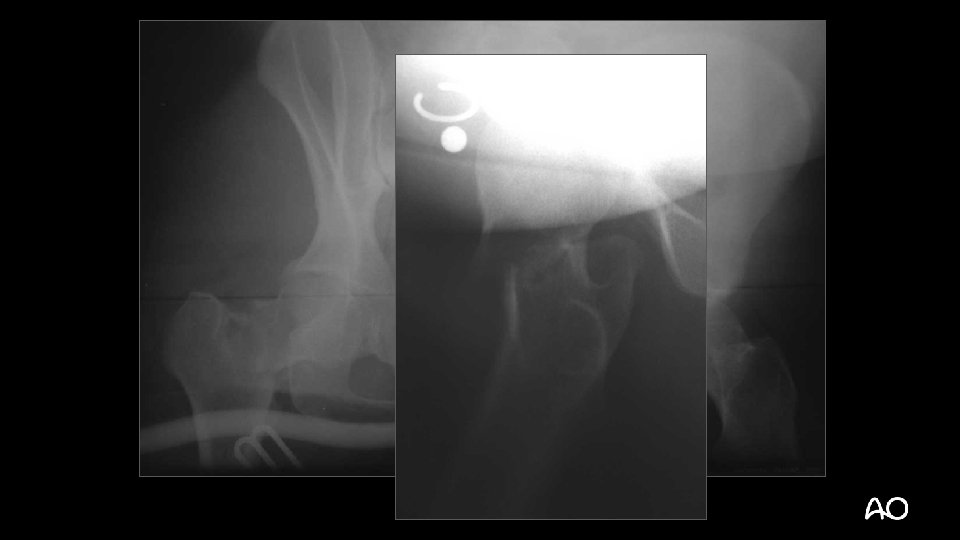

How would you manage this fracture?

Emergency surgery - Wound debridement - Percutaneous screw fixation femoral neck - Joint-bridging external fixator proximal femur distal tibia Transferred to tertiary trauma unit next day

Definitive surgery at 48 hrs - Wounds re-debrided Femoral external fixator removed ORIF femoral neck Bridge plating of femur shaft (LISS) Tibial external fixator removed Reamed, locked IM nail (tibia) Skin grafts at 96 hours